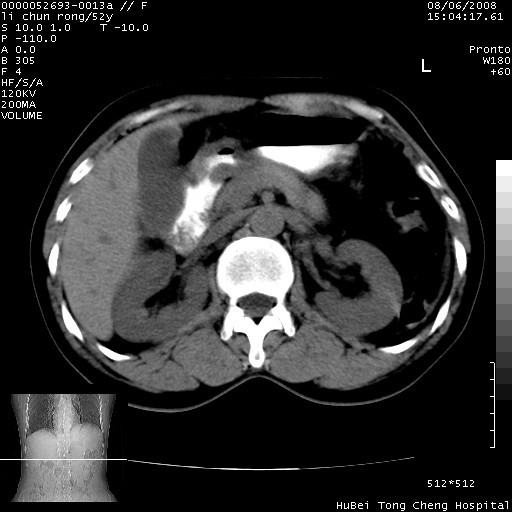

以下是引用云翔在2008-8-7 6:20:00的发言:[br]胰尾部囊性病变,考虑假囊肿,结合实验室检查疾病史

以下是引用zjzjr在2008-8-7 8:38:00的发言:[br]支持胰腺炎伴假囊肿形成,左肾小囊肿.少量腹水.

以下是引用随光逐影在2008-8-7 9:12:00的发言:[br]1)考虑胰腺炎伴假性囊肿形成可能性大;胰腺囊腺瘤待排。2)左肾小囊肿。3)少量腹水。